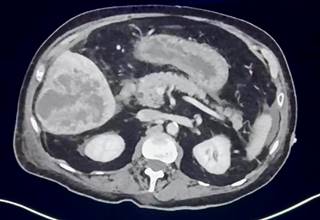

Mujer de 80 años con antecedente de enfermedad diverticular y viaje reciente a España. Inicia con dolor abdominal difuso de dos semanas de evolución que posteriormente se localiza en hipocondrio derecho, fiebre de 38.5 oC, hiporexia, astenia y adinamia. En el examen físico, dolor en hipocondrio derecho sin hepatomegalia. Se realiza tomografía axial computarizada (TAC) de abdomen con contraste intravenoso evidenciando abscesos hepáticos (Figura 1).

Figura 1: Tomografía de abdomen con contraste intravenoso con presencia de abscesos hepáticos de en el segmento V y VI de 84 × 78 × 66 mm en sus ejes máximos con un volumen aproximado de 206 cm3.